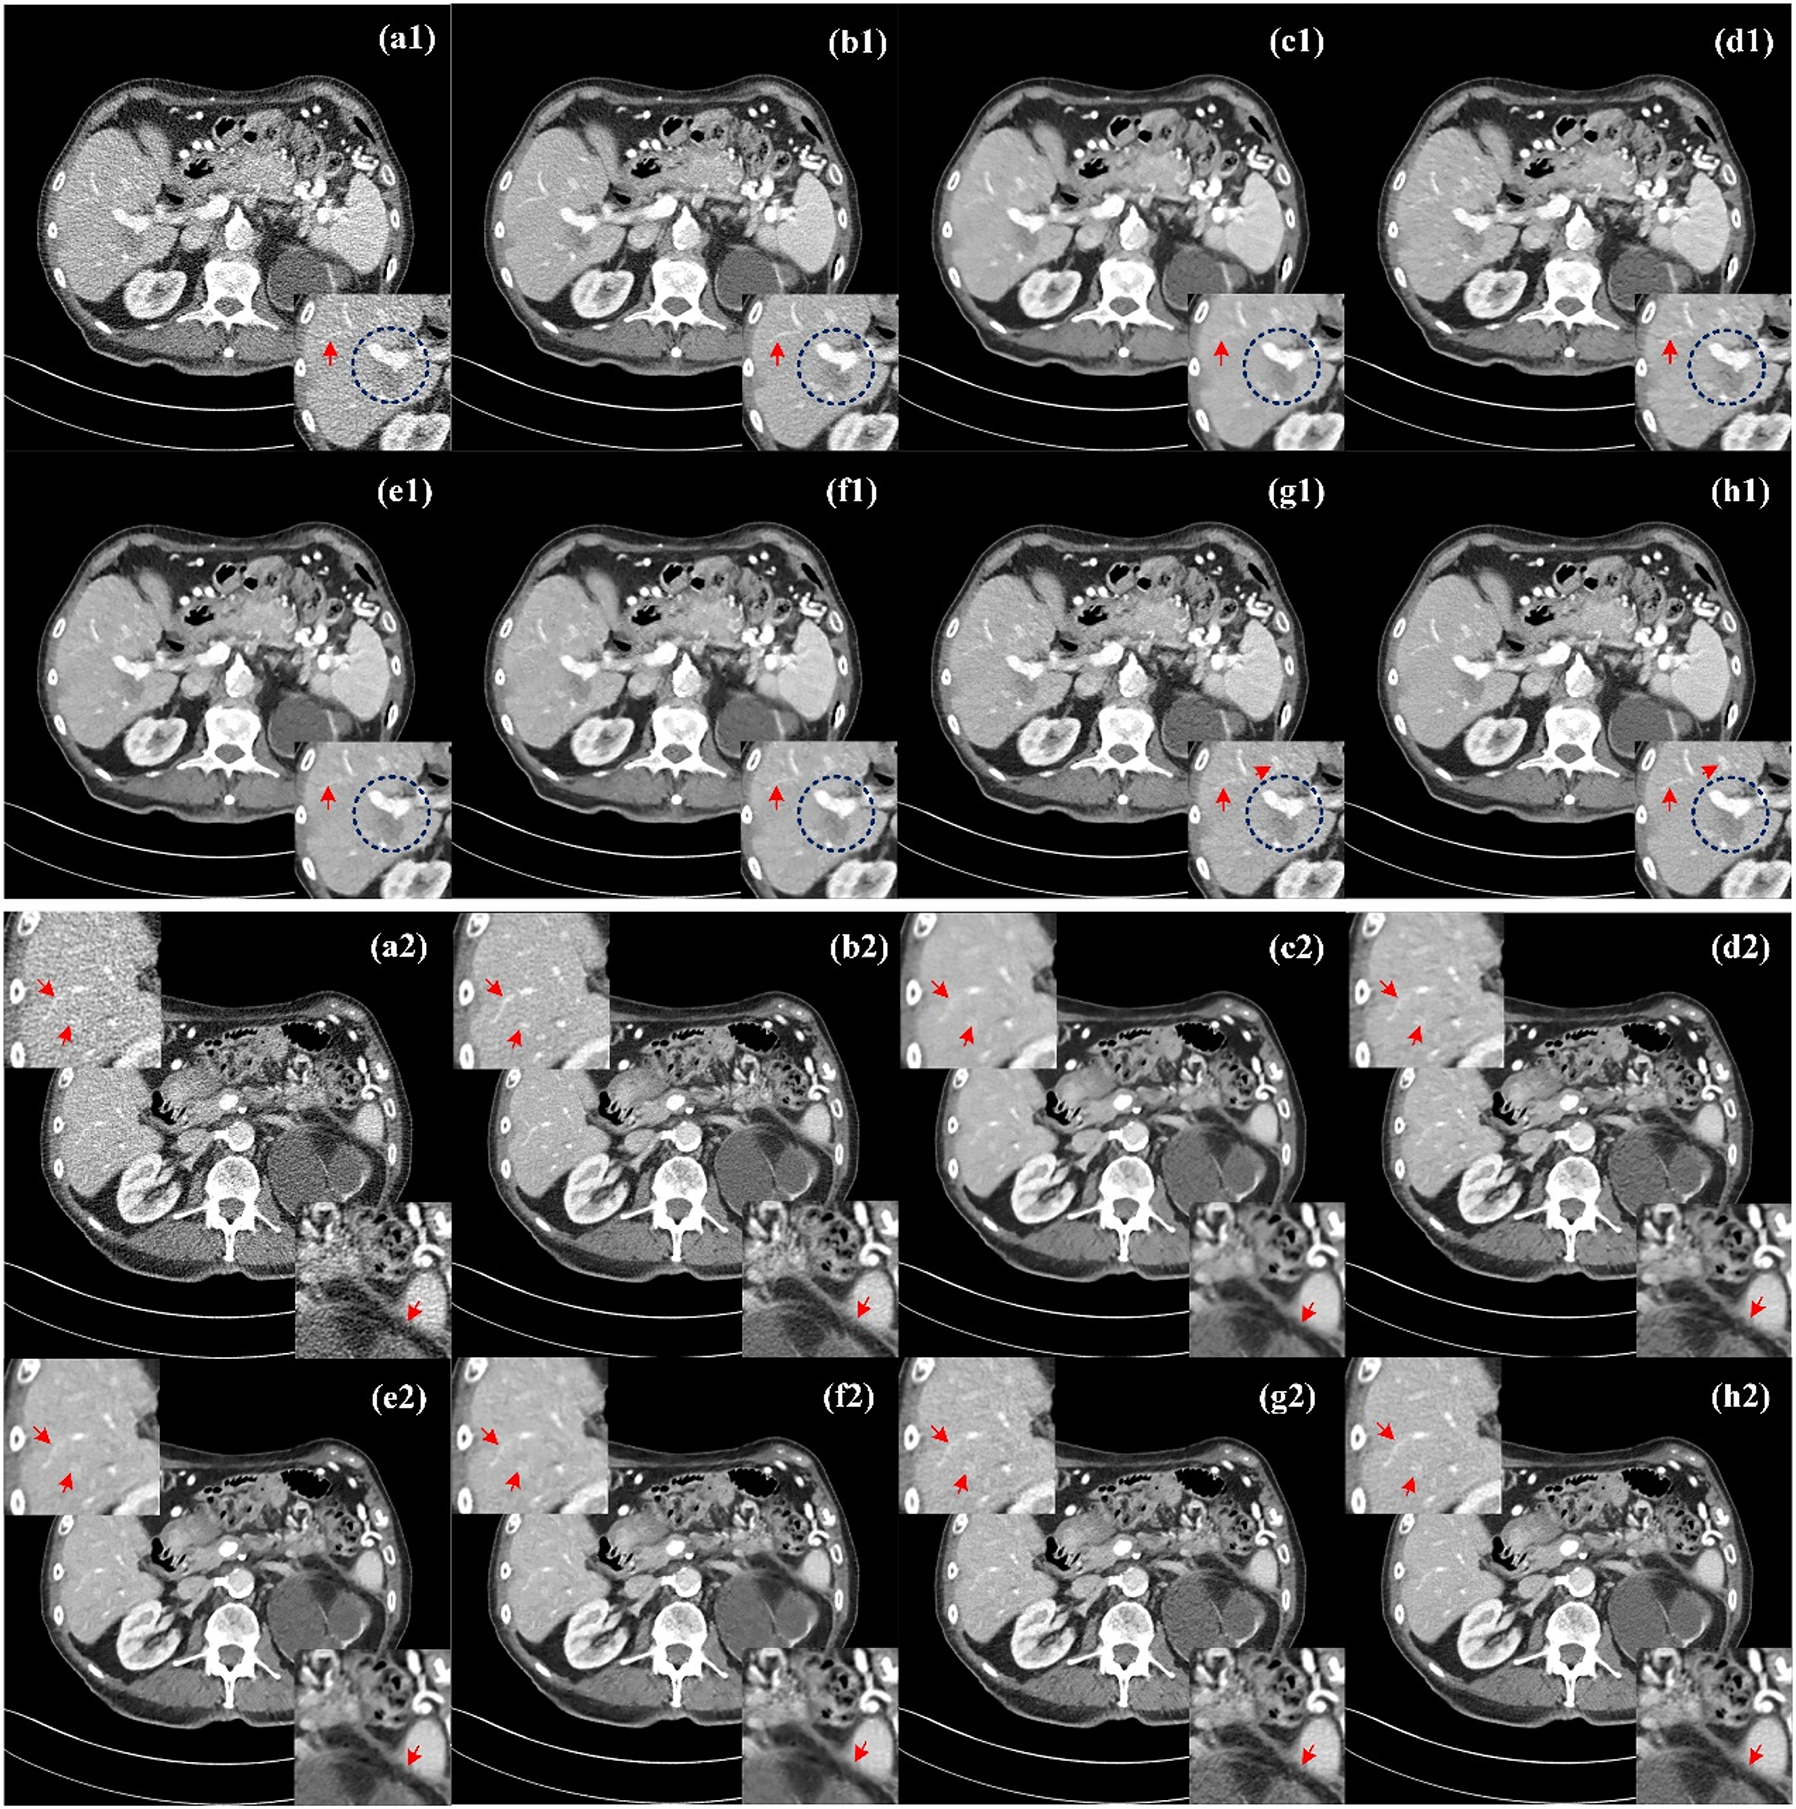

Mayo dataset visual assessment

Figure 4 show the processed results of two representative slices (denoted as Case 1 and Case 2) from the Mayo test dataset by different methods. All CT images of the axial view are displayed in the [−160, 240] HU window. Due to insufficient photons from incident X-rays, there are a lot of speckle noise and edge artifacts in LDCT images, making it difficult for physicians to determine clinically significant lesion information. From NDCT images (Figure 4(b1) and (b2)), clear lesions can be observed, but there are serious artifacts and noise in LDCT images, as shown in Figure 4(a1) and (a2), so it is difficult to sketch accurately. To show the noise reduction more clearly, we also zoom three ROI(region of interesting) areas (ROI1 in the lower right corner of Case 1, ROI2 in the upper left corner of Case 2, and ROI3 in the lower right corner) and marked them with red arrows and blue circles for better comparison. In general, these six methods can achieve a certain degree of denoising effect, and different denoising methods have different degrees of suppression of noise and artifacts in LDCT images.

Comparison of processed images by different methods for Case 1 and Case 2. (a1, a2) LDCT, (b1, b2) NDCT, (c1, c2) REDCNN, (d1, d2) QAE, (e1, e2) EDCNN, (f1, f2) CTformer, (g1, g2) CoreDiff, (h1, h2) CECDM. ROI1 in the lower right corner of Case 1, ROI2 in the upper left corner of Case 2, and ROI3 in the lower right corner.

In contrast, REDCNN (Figure 4(c1) and (c2)), while eliminating some noise, suffers from image blurring and images that are too smooth and texture details are lost, such as the details marked by the red arrow in ROI2, the upper left corner of Figure 4(c2). QAE (Figure 4(d1) and (d2)) and CoreDiff (Figure 4(g1) and (g2)) can significantly eliminate noise, and the detail retention effect is better than REDCNN to a certain extent, but the visual effect of these two methods is blurry. EDCNN(Figure 4(e1) and (e2)) and CTformer (Figure 4(f1) and (f2)) are better at preserving image detail than the other methods, but fine striped artifacts are still visible at the red arrows of ROI1 and ROI2. In contrast, CECDM achieves better results in effectively removing noise/artifacts and preserving tissue/structure. The lesion contours of ROI1 (blue circles shown in Figure 4(e1) and (h1)) are easy to identify. It can be found that the lesion contours of EDCNN and CECDM are the clearest, while those of other methods are fuzzy, which confirms the role of edge enhancement module. In addition, CECDM has the clearest tissue edges in ROI3 in Figure 4 (h2). Compared with other images in ROI3 in Figure 4, CECDM has the strongest ability to remove noise and artifacts, while other methods have significant residual artifacts. The results show that CECDM has good texture preservation and noise suppression ability.